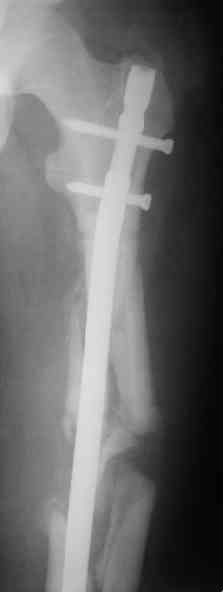

> денамизация - февраль 2006. ( 3 и 4 снимки) на сегодняшний день (снимок 5) беспокоит боли в тбс...

Однозначно: удалить, рассверлить, перештифтовать более толстым гвоздем. ЭТОТ 9 мм будет? Возьмите 12-14.

Дистально обязательно два винта! Проксимально можно один динамический. Больной будет счастлив на следующий же день!

Учитывая точку введения - верхушка б\вертела - что бы исправить варус взял бы соответствующий гвоздь: длинную Гамму или PFN или Recon

Судя по уровню перелома, винты в шейку избыточны, подойдет и диафизарный гвоздь. Все, что нужно, это тиски и труба. Загнуть сразу ниже отверстий градусов на 8-10, и вся недолга. Последние годы у нас это рутинная практика. Предызогнутые еще с завода гвозди неудобны тем, что они уже правый-левый.

Согласен, что 3,5 см укорочение этим снимкам не соответствует, за счет перелома и деформации - 1,5 см от силы. То есть либо ошибка измерения, либо приводящая контрактура, либо укорочение за счет другого отдела.

Согласен, что закрытый реостеосинтез с рассверливанием и коррекцией оси - это то, что надо. Мы бы ввели в центральный отломок статических 2-3 винта, и один динамический винт в дистальном отломке.